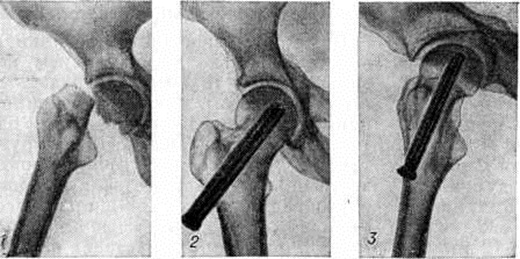

При выборе метода лечения Переломы (особенно оперативного) важно выяснить адаптационно-компенсаторные возможности и резервные силы организма. Пожилым ослабленным больным предпочтительно применять простые, легко переносимые и сравнительно безопасные приёмы лечения. Следует избегать методов лечения, вынуждающих длительно лежать в постели и затрудняющих передвижение. У данного контингента больных значительно возрастает степень операционного риска. Поэтому оперативное вмешательство по поводу Переломы у пожилых людей нужно применять тогда, когда консервативные методы не эффективны, а также в тех случаях, когда оперативный способ может быть легче перенесён больным, чем консервативный. Оперативное лечение наиболее часто применяют при аддукционных (варусных) медиальных Переломы шейки бедренной кости. В этих случаях показан остеосинтез трёхлопастным гвоздём или другим фиксатором, а также эндопротезирование (рисунок 12 и 13). При соответствующих показаниях вертельные и диафизарные Переломы бедра также лечат оперативно.

Рис. 12.

Рентгенограммы тазобедренного сустава с медиальным переломом шейки бедра: 1— до операции (видно смещение отломков), 2— прямая и 3— боковая рентгенограммы после остеосинтеза трёхлопастным гвоздём.

Рис. 13.

Прямые рентгенограммы тазобедренного сустава при переломе шейки бедра: 1— до операции; 2— после эндопротезирования головки и шейки бедра.